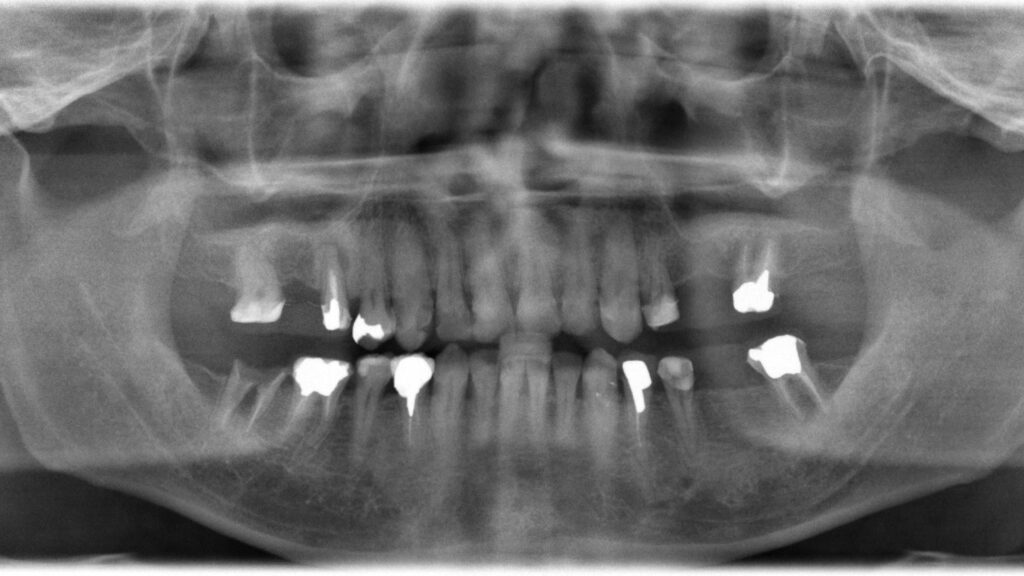

奥歯は傷みが酷く、確実にかみ合わせを支えるためにもインプラント治療となりました。後日インプラントオペの際は抜歯した歯牙に大量の膿が発生しておりました。

| 診断名 | 咬合不良・審美障害・う蝕 |

| 抜歯部位 | 14,25,27,37,46,47 |